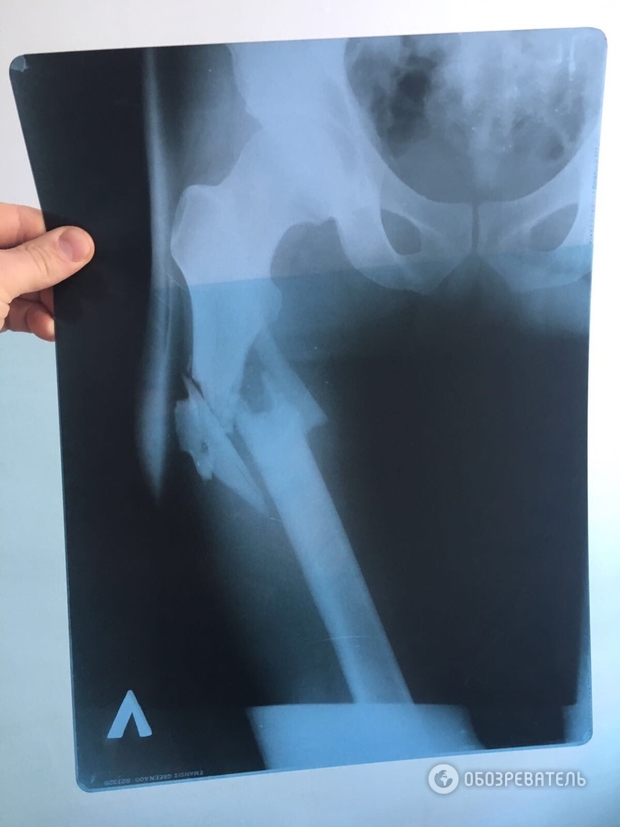

Лікар, що оперував В’ячеслава Хімікуса, якого поранив з пістолета народний депутат Сергій Пашинський, на допиті підтвердив, що на місці перелому у потерпілого уламки кістки зміщені вниз від таза.

Він також наголосив, що цей факт підтверджує, що Пашинський вистрілив зверху в ногу Хімікусу, а не з положення лежачи, як нардеп стверджував раніше.